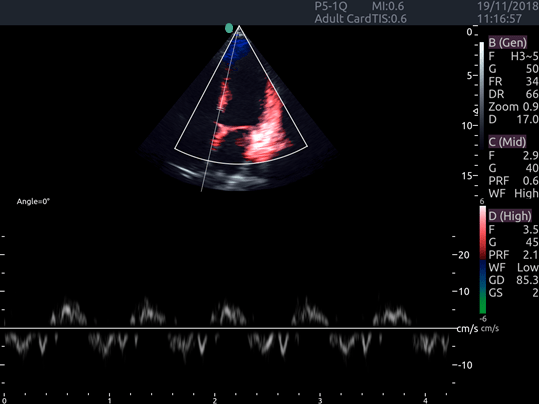

Invictus E5

O ultrassom Invictus E5 apresenta um design moderno e exclusivo, com perfeito fluxo de trabalho e interface intuitiva.

Dentre suas características inovadoras, podemos destacar a tela em LCD com rotação de 60° para ambos os lados, para otimização da visualização durante os exames; tela touch screen com menu totalmente customizável; painel de controle totalmente selado para facilitar limpeza e desinfecção da superfície, o que o torna referência para ser utilizado principalmente em Centro Cirúrgico.

Apresenta excelente qualidade de imagem, trabalho otimizado através de presets pré-determinados, sensibilidade e eficiência em aplicações de Point of Care e portanto, uma perfeita relação custo benefício.